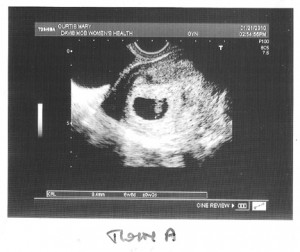

Before I go to sleep, I’ll post the first images and stats of our twins below – twin A (lower in the uterus) and twin B. Love you all!